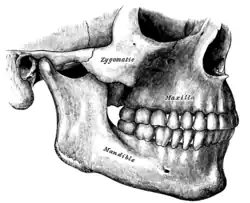

Maxilas em verde. Vista lateral.

Maxilas em verde. Vista lateral. -

Superfície lateral esquematizada.

Superfície lateral esquematizada. -